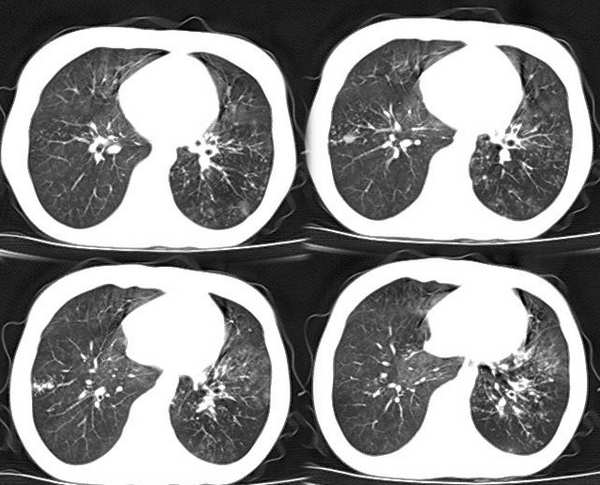

以下是引用x线在2006-2-2 17:37:00的发言:[br]结合病史支持“ct拟诊:双侧tb,左下叶结核球,左下叶局限性轻度支扩。”双下叶及左舌叶淡薄的毛玻璃密度影,我考虑为炎性渗出。另:是否合并霉菌感染须进一步检查确定。